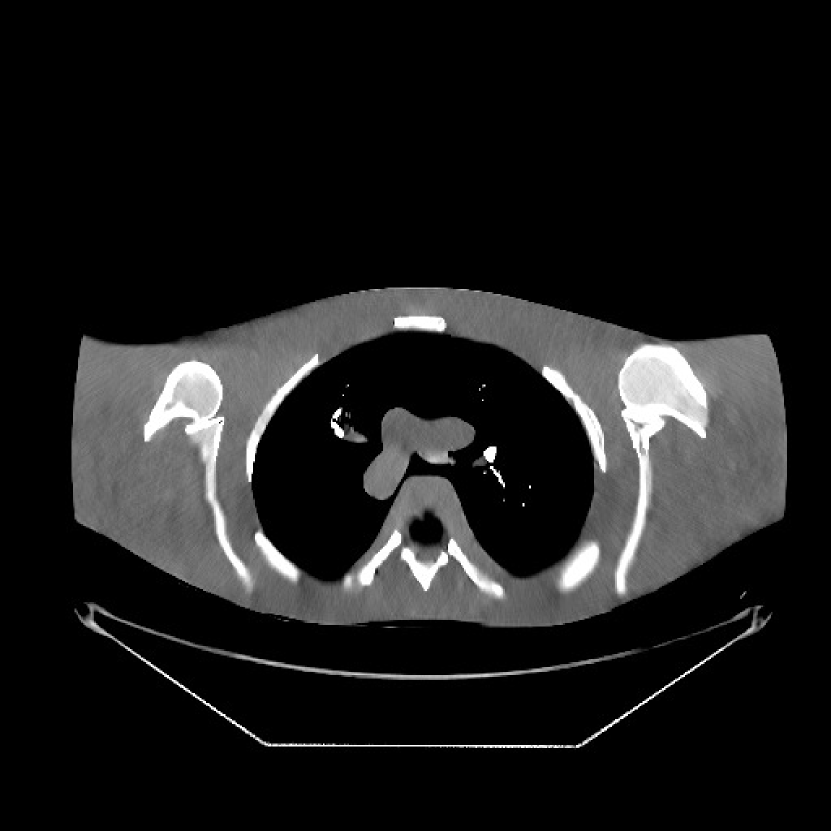

Fig. 9 shows three axial slices from the 3D reconstructions with SPULTRA and PWLS-ULTRA at : the middle slice (No. 67) and two slices located farther away from the center (No. 90 and No. 120). The image profiles along a horizontal line (shown in green) in the displayed slices are also shown in Fig. 9. The reconstructed slices using PWLS-ULTRA appear darker around the center compared to the “true” clinical image and the reconstructions with SPULTRA. This means PWLS-ULTRA produces a strong bias in the reconstruction. The bias can be observed more clearly in the profile plots: the pixel intensities for the SPULTRA reconstruction better follow those of the “true” clinical image, while those for the PWLS-ULTRA reconstruction are much worse than the “true” values. Moreover, SPULTRA achieves sharper rising and failing edges compared to PWLS-ULTRA. In other words, SPULTRA also achieves better resolution than PWLS-ULTRA. Fig. 9 also shows a zoomed-in ROI for each of the chosen slices, and highlights some small details with arrows. It is clear that in addition to reducing the bias, SPULTRA reconstructs image details better than PWLS-ULTRA.